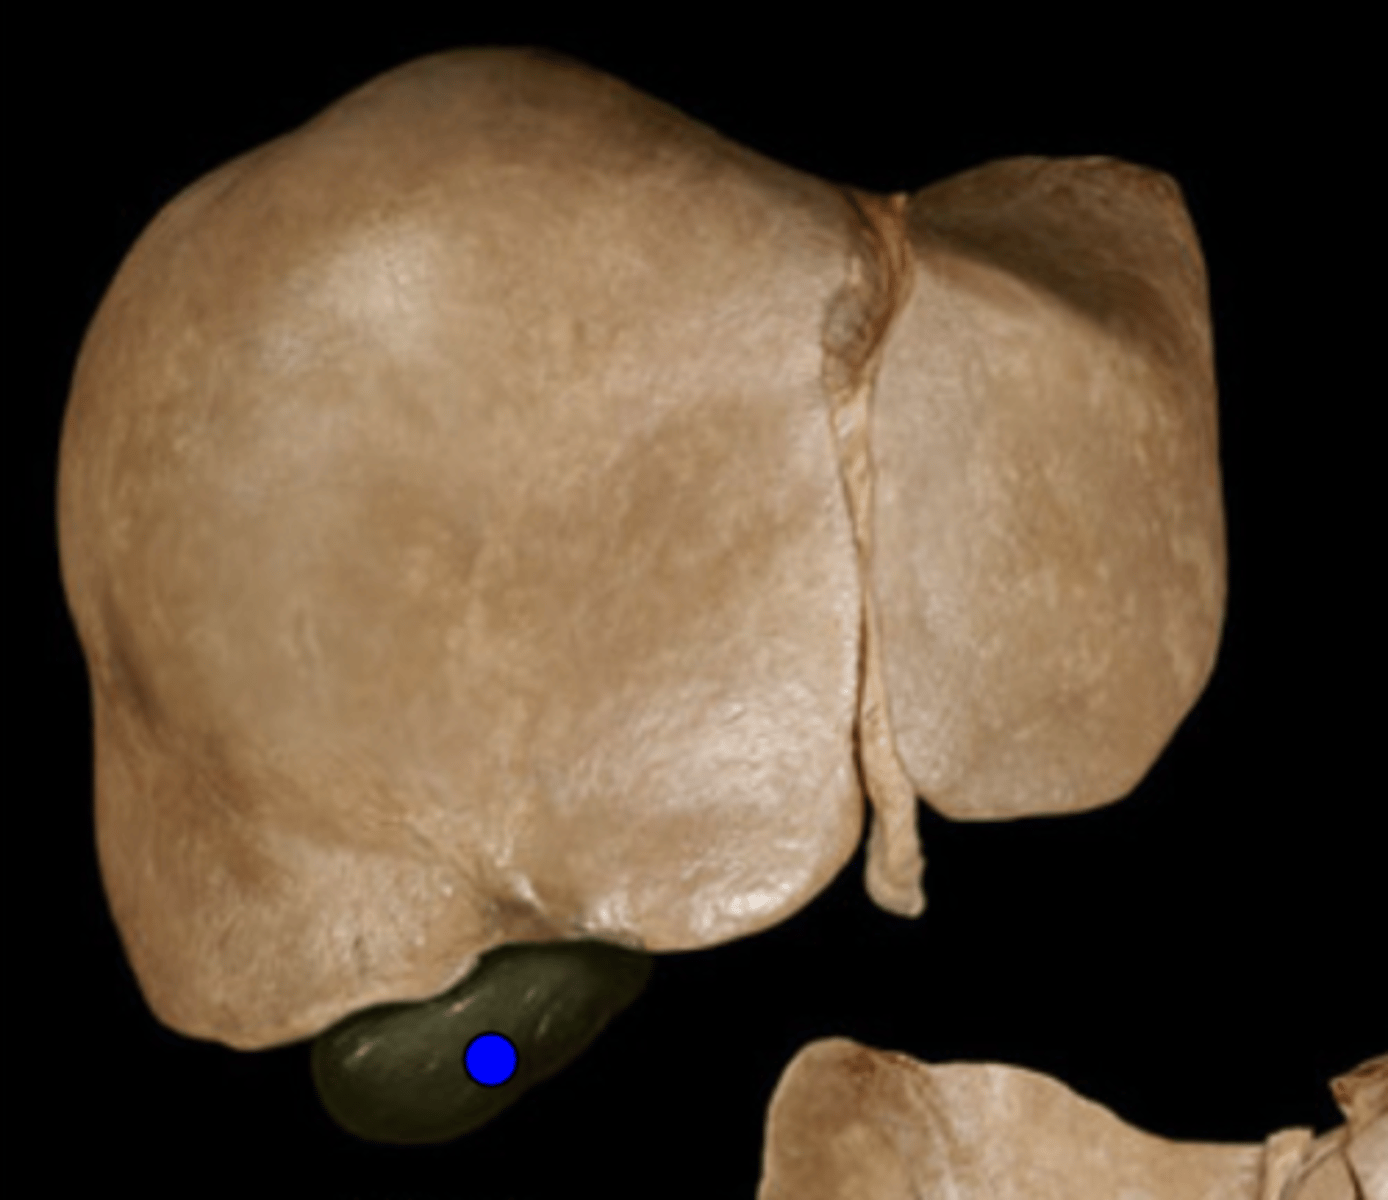

Right Lobe of Liver

Gall Bladder